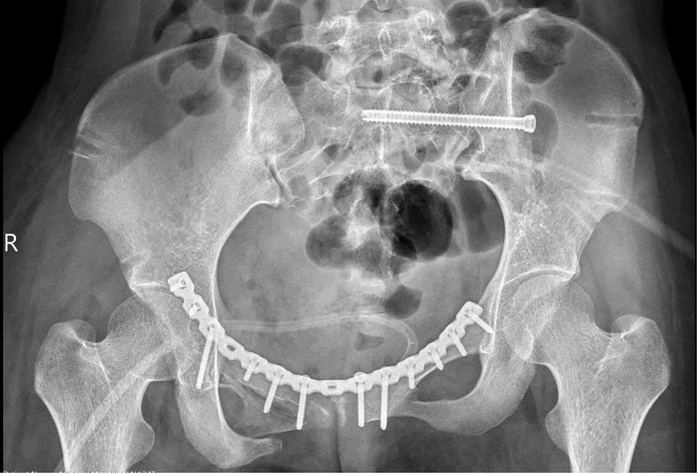

Bác sĩ đã phẫu thuật khẩn, ngăn chặn được tình trạng sốc đa chấn thương, cầm máu thành công và giành lại sự sống cho người bệnh. Sau 2 tuần điều trị tích cực, bệnh nhân được tháo cố định ngoài và phẫu thuật lần hai để nắn chỉnh lại các di lệch (có sử dụng công nghệ in 3D giúp tiên lượng mức độ khó của phẫu thuật và chọn các nắn chỉnh khung chậu và vị trí đặt nẹp) kết hợp xương bằng nẹp vít bên trong, giúp cố định vững chắc khung chậu. Hiện bệnh nhân có thể ngồi dậy và xuất viện về nhà.

Hình ảnh chụp Xquang của bệnh nhân sau phẫu thuật

"Ở trường hợp này, khung chậu mất vững cả cung trước và sau nên sau khi nắn chỉnh, chúng tôi cố định cung trước bằng nẹp vít và cung sau bằng vít xốp" – BS Khanh cho hay.